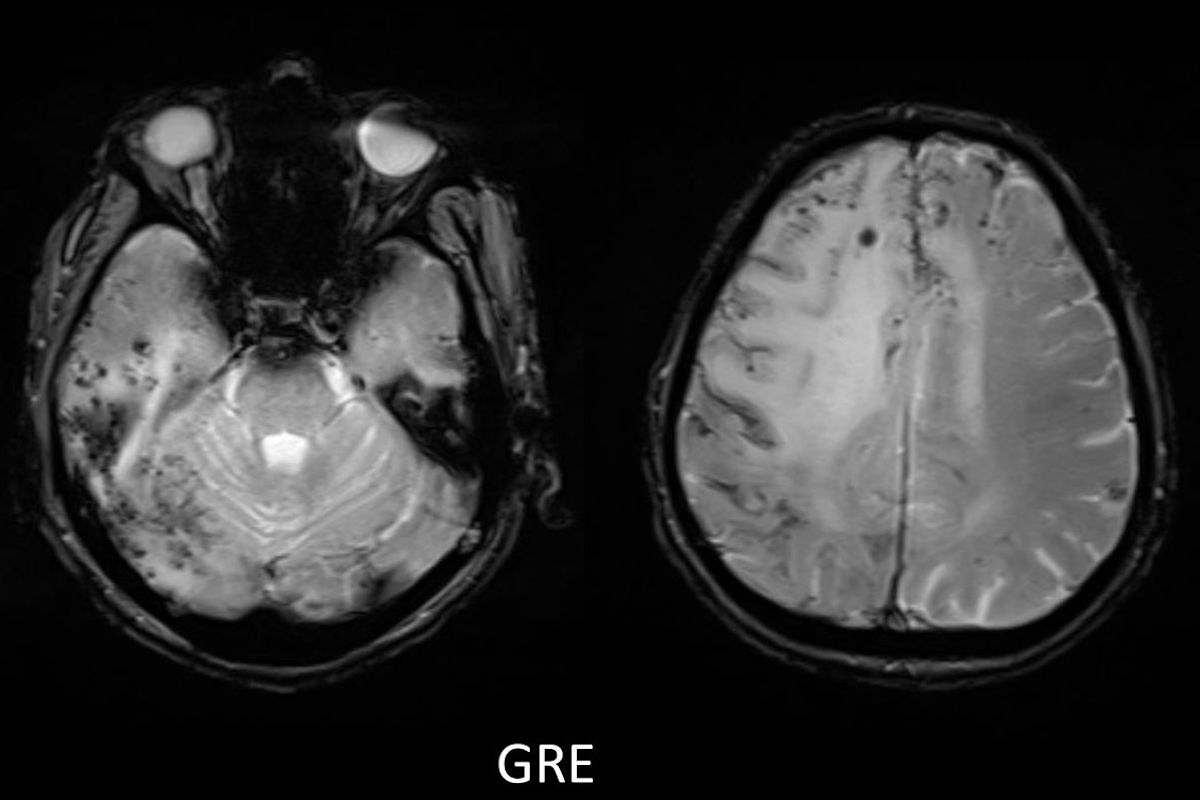

- C) Gradient seride milimetrik hemosiderin kalıntıları ve süperfisyal siderozis (kırmızı ok)

- Difüzyon kısıtlılığının olmaması, leptomeningeal kontrastlanma, FDG-PET’te düşük aktivite, GRE sekansta yaygın hemosiderin kalıntılarının eşlik etmesi ile karakterizedir.

- 40 yaş üzeri bilinç bozukluğu, davranış değişikliği, fokal nörolojik bulgular, bulguların akut intrakraniyal kanama ile doğrudan ilişkilendirilmemesi, subkortikal beyaz cevhere uzanan asimetrik unifokal ya da multifokal kortiko-subkortikal ödemli lezyonlara serebral mikro/makrokanama, superfisiyal siderozisin eşlik etmesi halinde mutlaka düşünülmelidir.